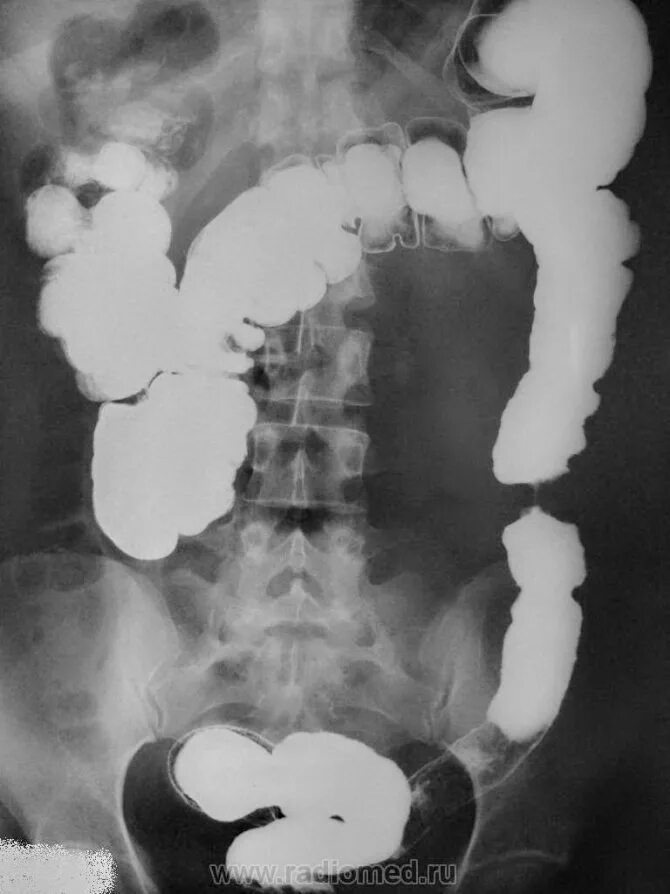

Непроходимость кишечника при онкологии